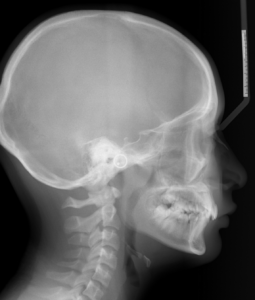

A 12 year old Asian female presents with a chief concern that “my teeth are crooked and I have a tooth stuck”